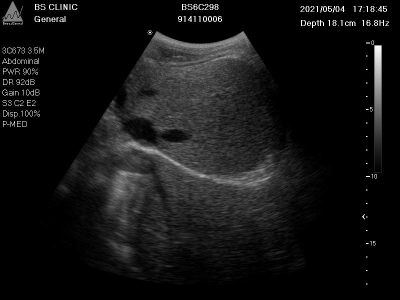

上图展示了一张典型的膈肌超声影像图,图像中红色框清晰标注了膈肌位置。膈肌在超声图像中表现为一条连续、略呈弧形的强回声带,位于肝脏或脾脏等腹腔器官与胸腔的分界处。通过分析膈肌的形态、位置及回声特征,可以评估膈肌完整性、厚度、活动度等指标,对诊断膈肌病变(如膈疝、膈肌麻痹)具有重要价值。

本数据集为Diaphragm数据集v7版本,采用CC BY 4.0许可协议,由qunshankj平台用户提供并导出。数据集包含315张腹部超声检查图像,所有图像均以YOLOv8格式标注,专注于膈肌(Diaphragm)的识别与定位。每张图像均为BS CLINIC机构的临床超声检查结果,设备型号为BS6C298,包含患者编号、检查时间、扫描深度(约16.8-18.1cm)、频率(16.8Hz)等临床参数。左侧参数栏详细记录了探头类型(如3D/7-3.5M、3CD73 SSM等)、检查部位(Abdominal腹部)、功率(PWR 90%)、动态范围(DR 92dB)、增益(Gain 100-108)、滤波设置(LB 0.2/C2 E2、G8 C2 E2等)及显示模式(Disp 100%、P-MED)等技术参数。图像主体呈现典型的腹部横断面超声灰度影像,清晰显示腹腔内不同组织的回声差异,包括低回声区和高回声结构。膈肌在图像中表现为弧形高回声带,通过红色多边形轮廓线精确标注,明确标识这一区分胸腔与腹腔的重要解剖结构。右侧刻度标尺用于测量深度,整体图像质量良好,细节可辨,为临床诊断提供膈肌位置、形态及周围组织关系的可靠参考。数据集未应用任何图像增强技术,保持了原始临床数据的真实性,适用于膈肌超声影像的自动检测算法研究与模型训练。

图1:典型的膈肌超声影像,红色区域为算法识别的膈肌轮廓